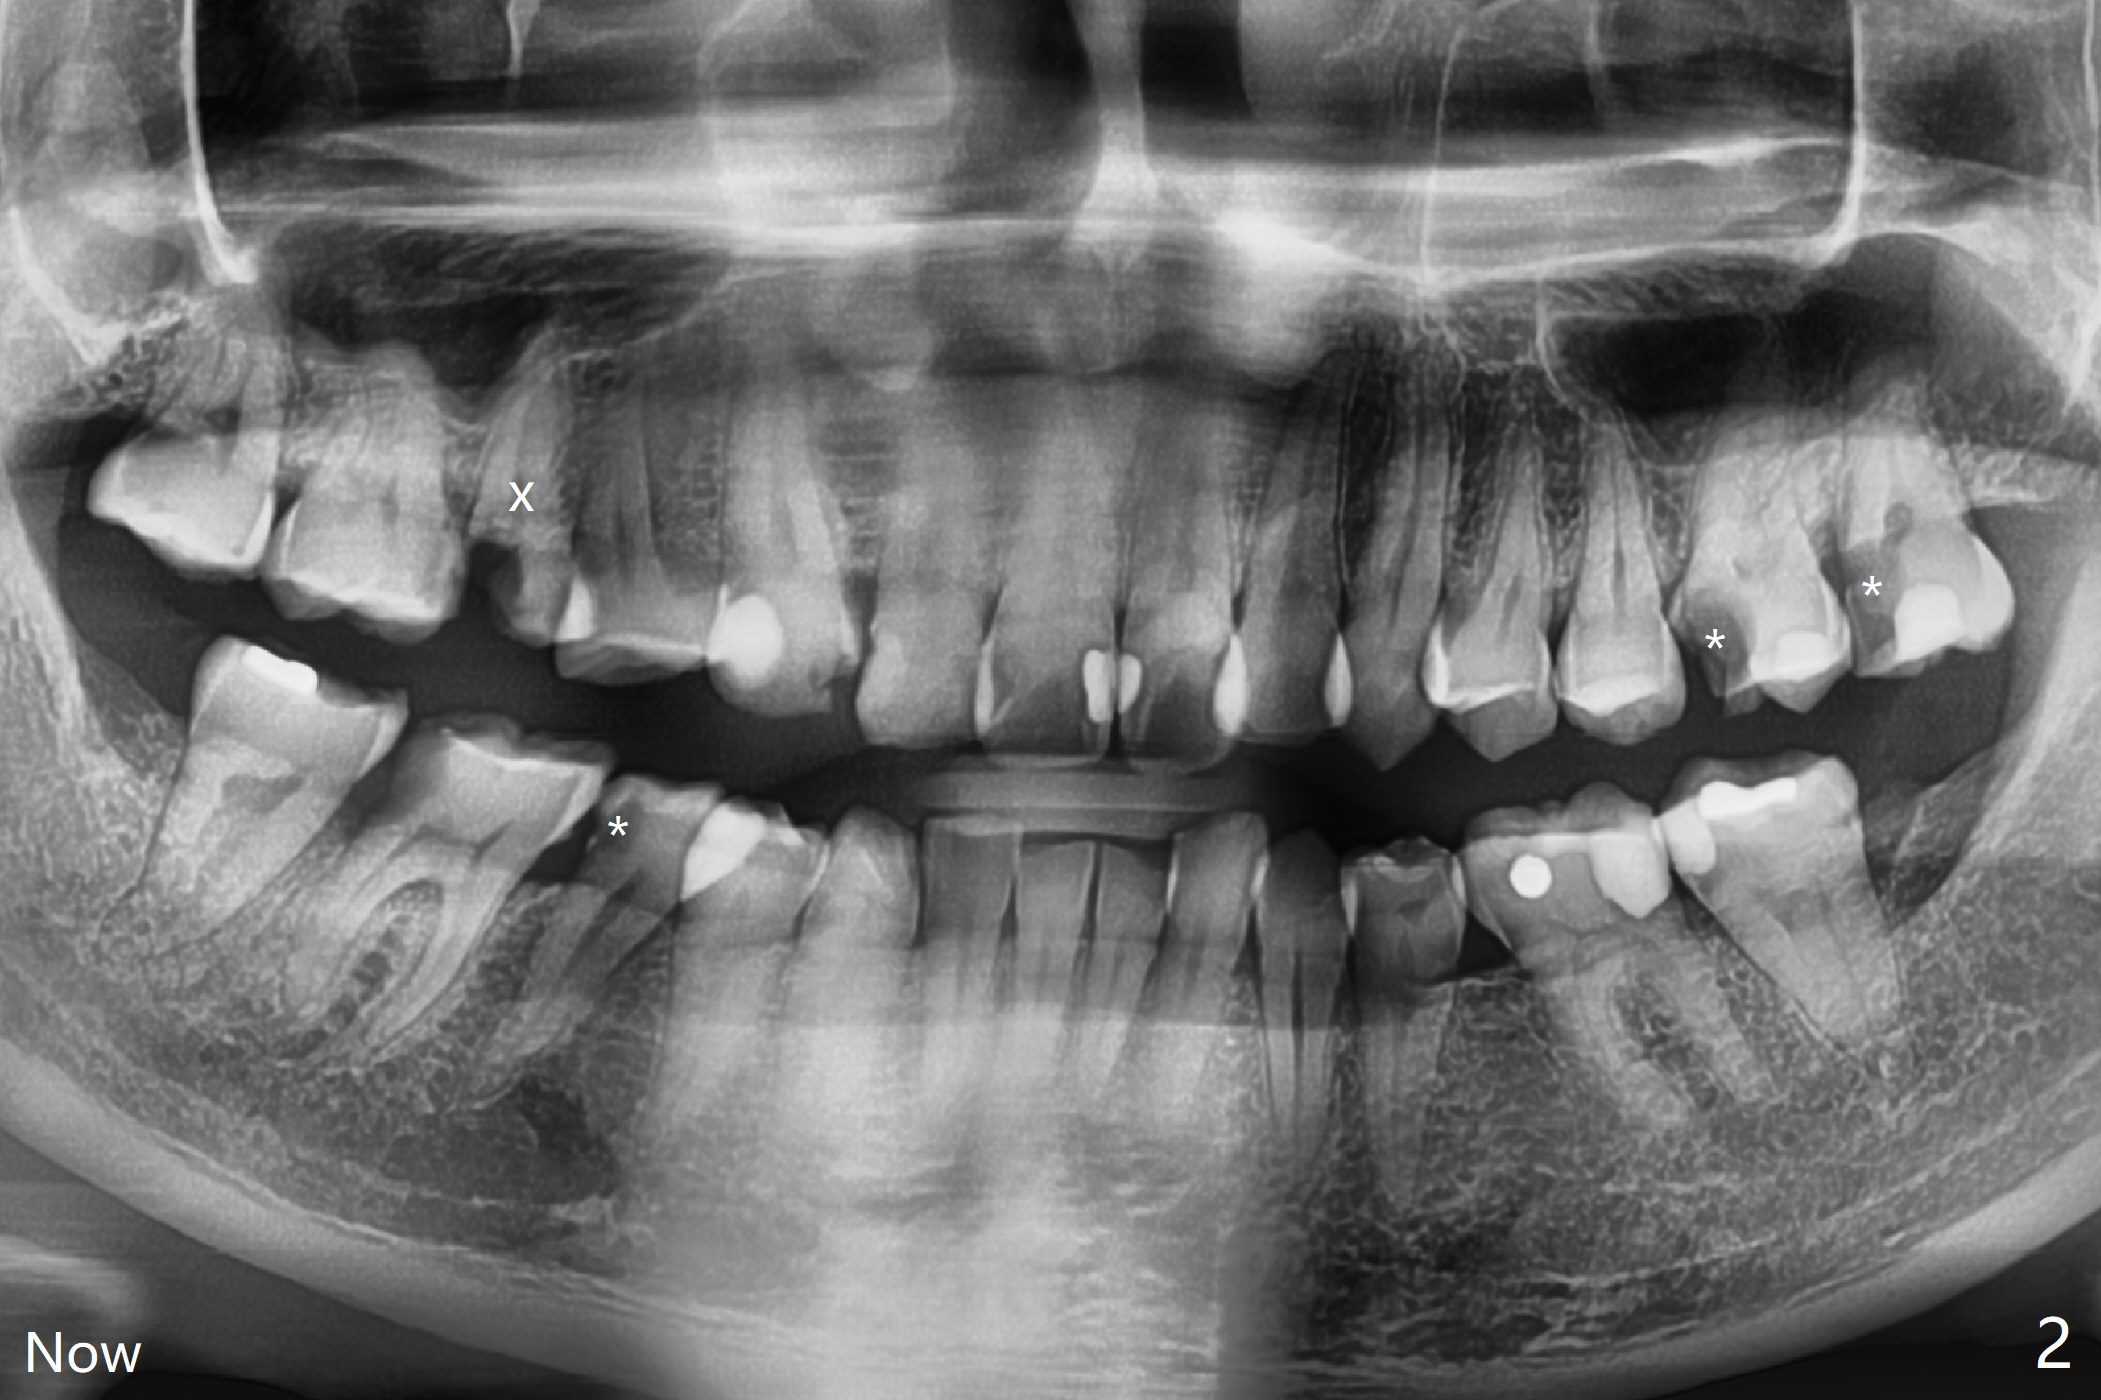

A 32-year-old man has had severe crowding for the last 10 years (Fig.1-5).  He is ready for orthodontic treatment now.  LL5 has been extracted for 4 years (Fig.1 x).  Severe caries at UR5 makes it easy to decide for extraction (Fig.2 x), while it is hard to determine which of the LR bicuspids needs to be extracted because of moderate caries at LR5 and even harder for UL because of caries at UL6,7 (Fig.2 *).

In fact impression for models (Fig.3-7) is taken after UL caries control.  Sedative filling is done at UL1,3 (Fig.6 *) and definitive restoration will be done when crowding resolves.  The defects at UL6,7 (Fig.6 x) is so extensive that after composite molar bands are placed immediately for retention.  Amazingly, there is no symptom after UL6,7 restoration.  Therefore UL4 will be extracted for crowding resolution.  UR 5 (Fig.1-3,6) has been extracted, while LR5 (Fig.2,7) will be.